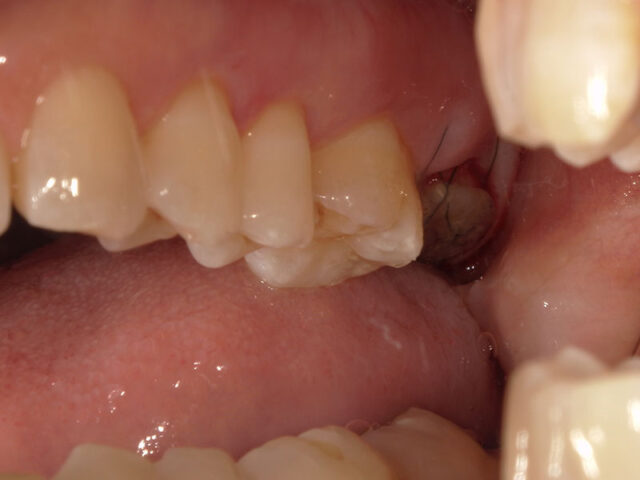

初診

左上7が真っ二つに割れています

初診時